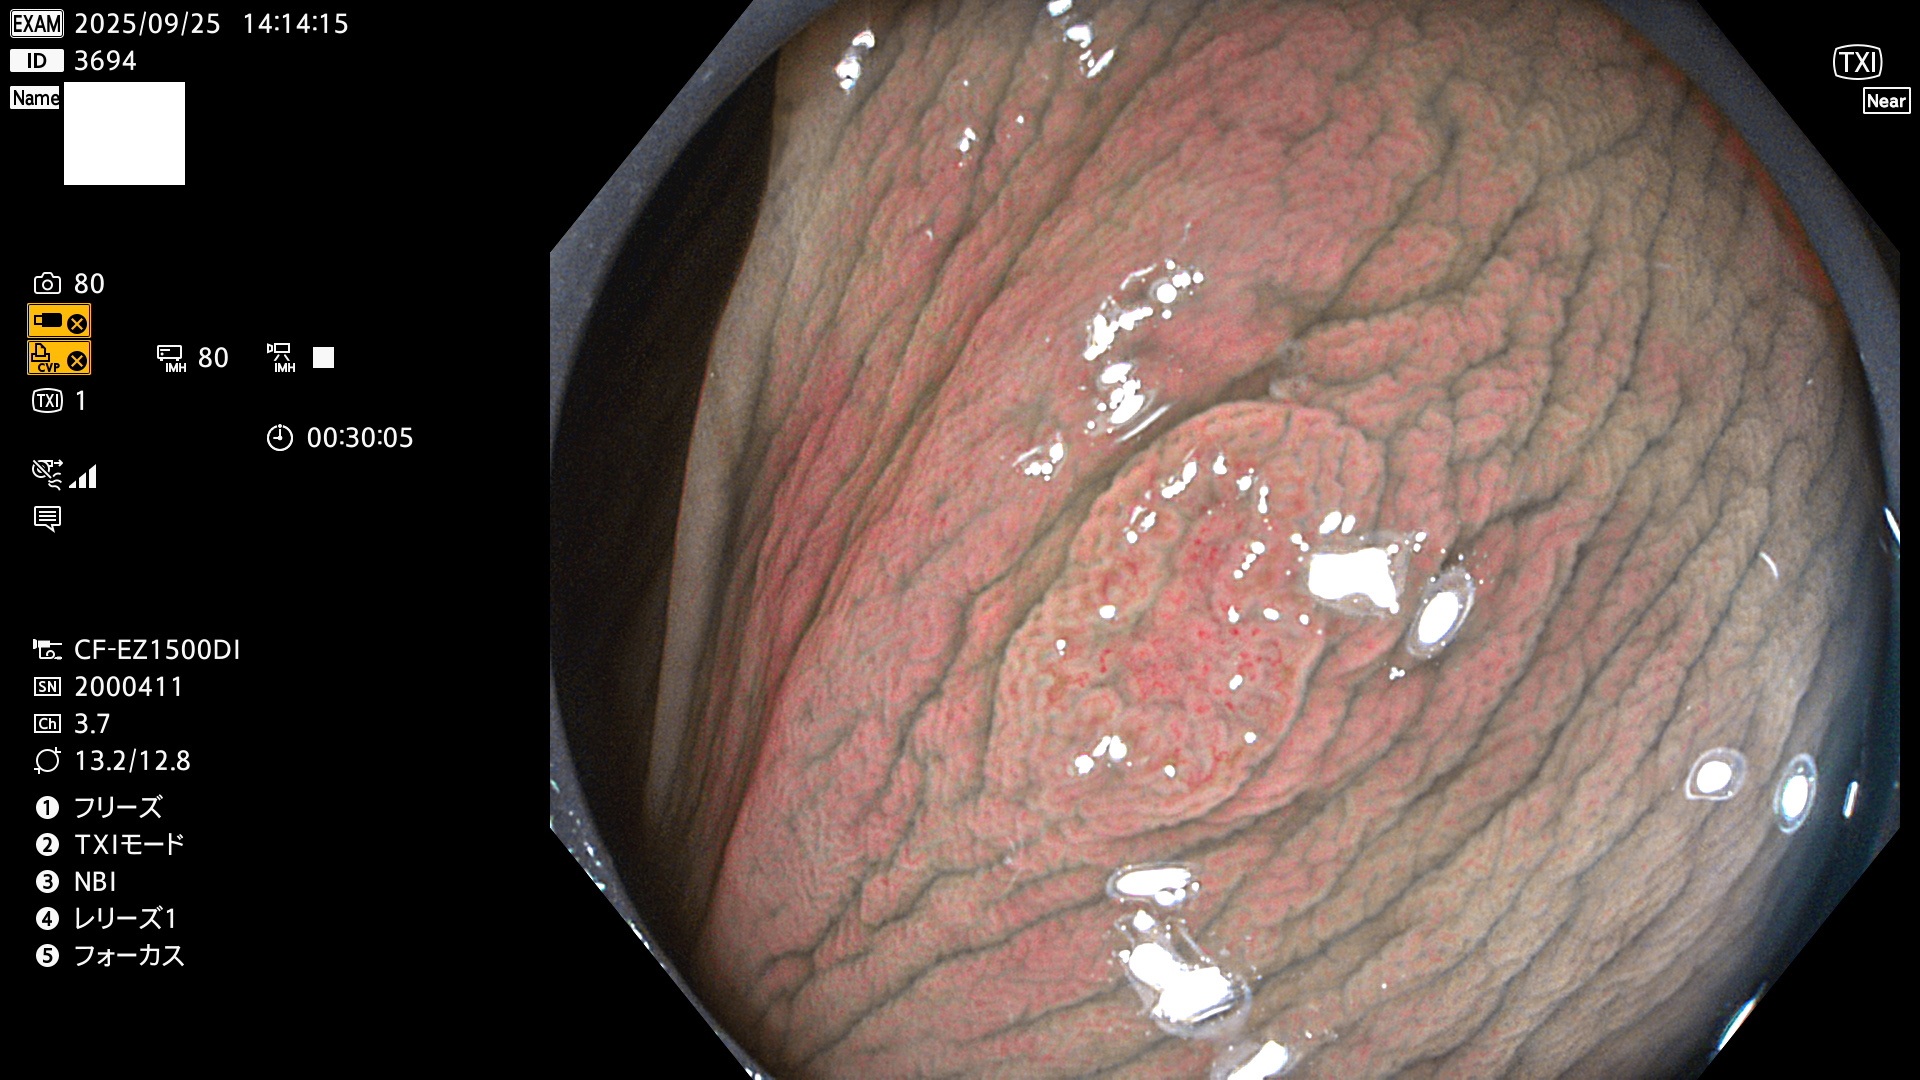

2025年9月25日〜9月28日の4日間(40件)4個 (Uc_ADR=4個/40人=10%)

2025年9月25日〜9月28日の4日間(40件)で4個 (Uc_ADR=4個/40人=10%)